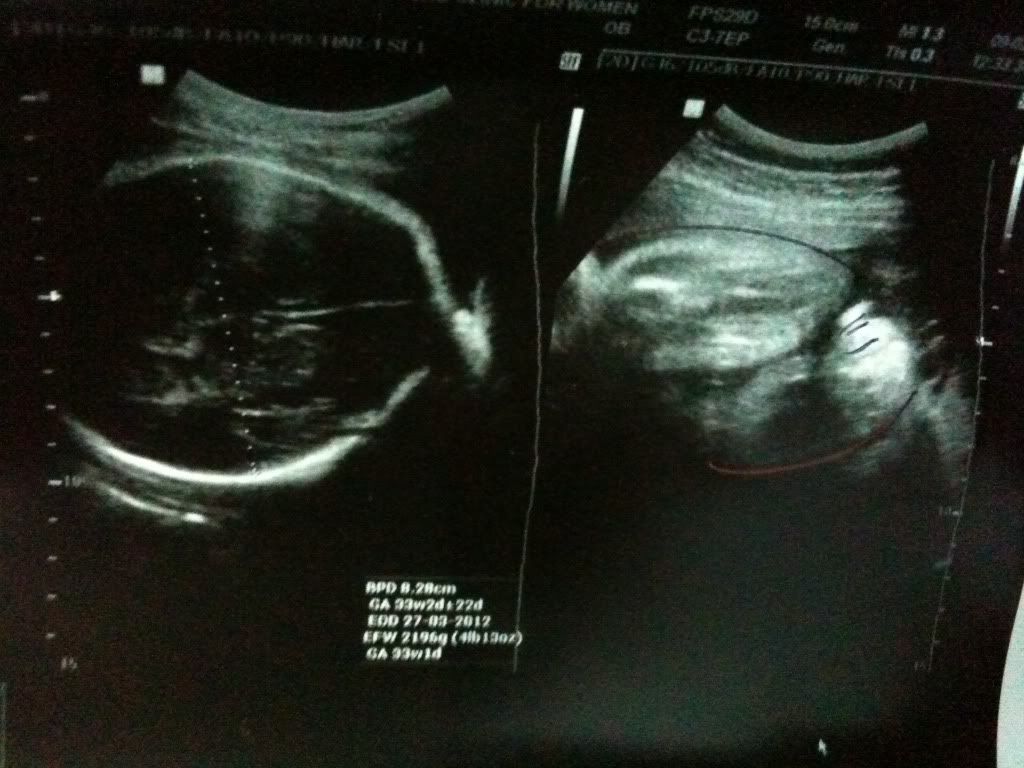

我是早你几天预产期的。。那天32周6天( 3/3/12)去check up baby 才2008g 而已。。从28周起她的头就在下面了。。应该不会转上了吧。。很快下个月就要生了。。希望我们俩顺产哦。。 |